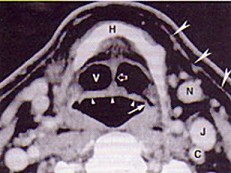

男,55歲,聲嘶6年,有長期吸煙史。檢查:無呼吸困難。喉鏡檢查:聲帶慢性充血,可見右側(cè)聲帶可見菜花樣新生物,右側(cè)聲帶活動(dòng)固定,喉部CT檢查如下圖: